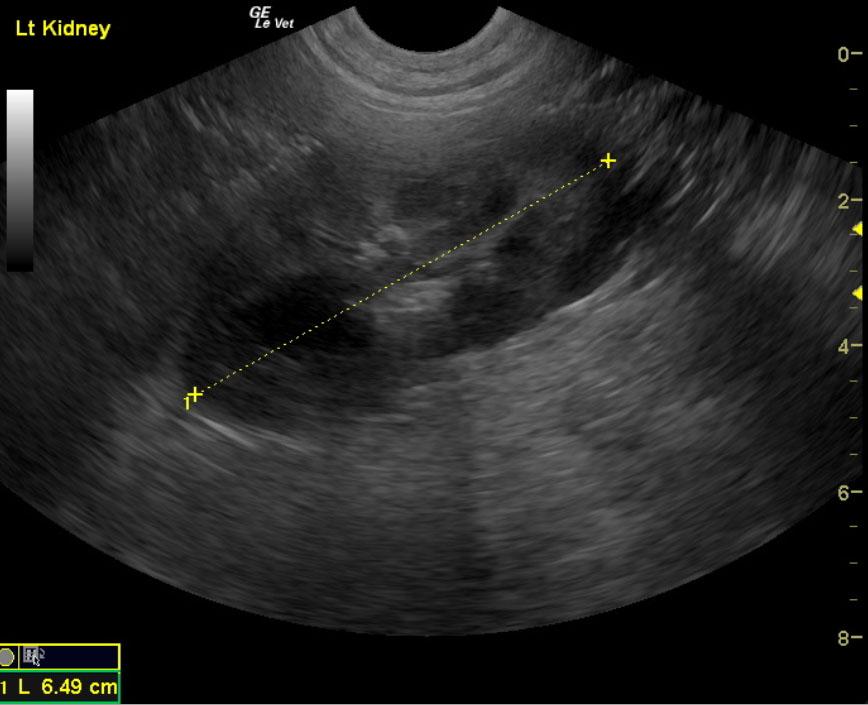

The kidneys in this patient had a persistent, slightly irregular contour, with the left kidney demonstrating slight pyelectasia (0.26 cm). The urinary bladder, trigone and pelvic urethra presented normal wall thicknesses with anechoic urine and normal tone. The urinary bladder revealed slight calculus at 0.23cm, yet was not shadowing. No evidence of inflammatory or neoplastic changes were noted.